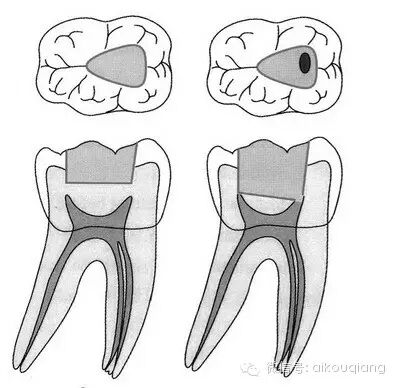

“G型扩孔钻预备:应用GG钻预备根管冠2/3可获得良好的根管冠部通道。GG钻进人根管前,一定要用10#或l5#根管锉探查和通畅根管,如果GG钻1#进入根管有困难时,应初步预备根管,再使用GG钻进入。一般来说,GGl#进入根管l6~17mm;GG2#,GG3#后退2~3mm;GG4#进入根管口下2~3mm;GG5#,GG6#仅作根管口以上部分预备,便于髓腔与根管口形成直线通道。GG钻勿进入根管的深部,避免过度去除牙本质,造成根管壁的薄弱,形成穿孔或瓶颈样预备(见下图)

图 根管的瓶颈样预备(右图)